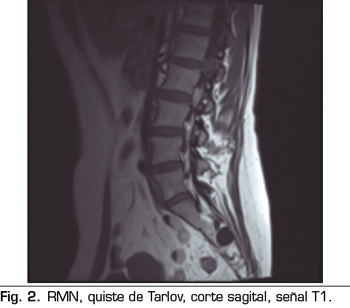

Los “quistes perineurales” o “Quistes de Tarlov” son alteraciones en la duramadre de las raíces nerviosas, que se producen más frecuentemente en la zona sacra. El diagnóstico suele ser casual mediante RMN; la incidencia es variable, debido a que el hallazgo es incidental. Habitualmente son asintomáticos, pero pueden producir radiculopatía, dolor perineal o vejiga neurógena, entre otros.

The diagnosis is usually casual by magnetic resonance. The incidence is variable, because the finding is incidental. The are usually asymptotic, but can cause radiculopathy, perineural pain or neurogenic bladder.

Figura 1